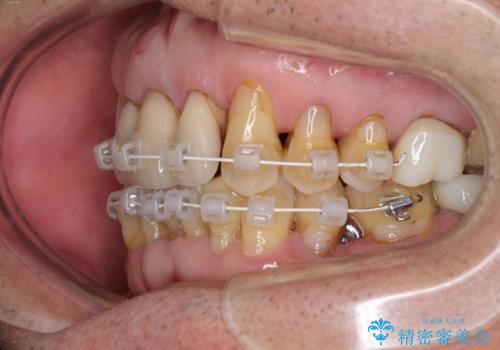

矯正治療と歯周外科処置を併用した審美歯科治療

- 上の前歯が痛むとのことで来院された患者様です。

検査を行ったところ、前歯1本は周辺の骨が失われており、抜歯が必要でした。

上顎の奥歯は全体的に歯周ポケットが散見され出血が認められたため、歯周外科処置を行うこととしました。

上の歯は見た目を良くしたいというご希望があったため、歯周外科処置を行った歯についてはセラミッククラウンで補綴することとしました。

また、前歯の部分矯正も希望されたため、歯周外科処置と平行して矯正治療を行うこととしました。